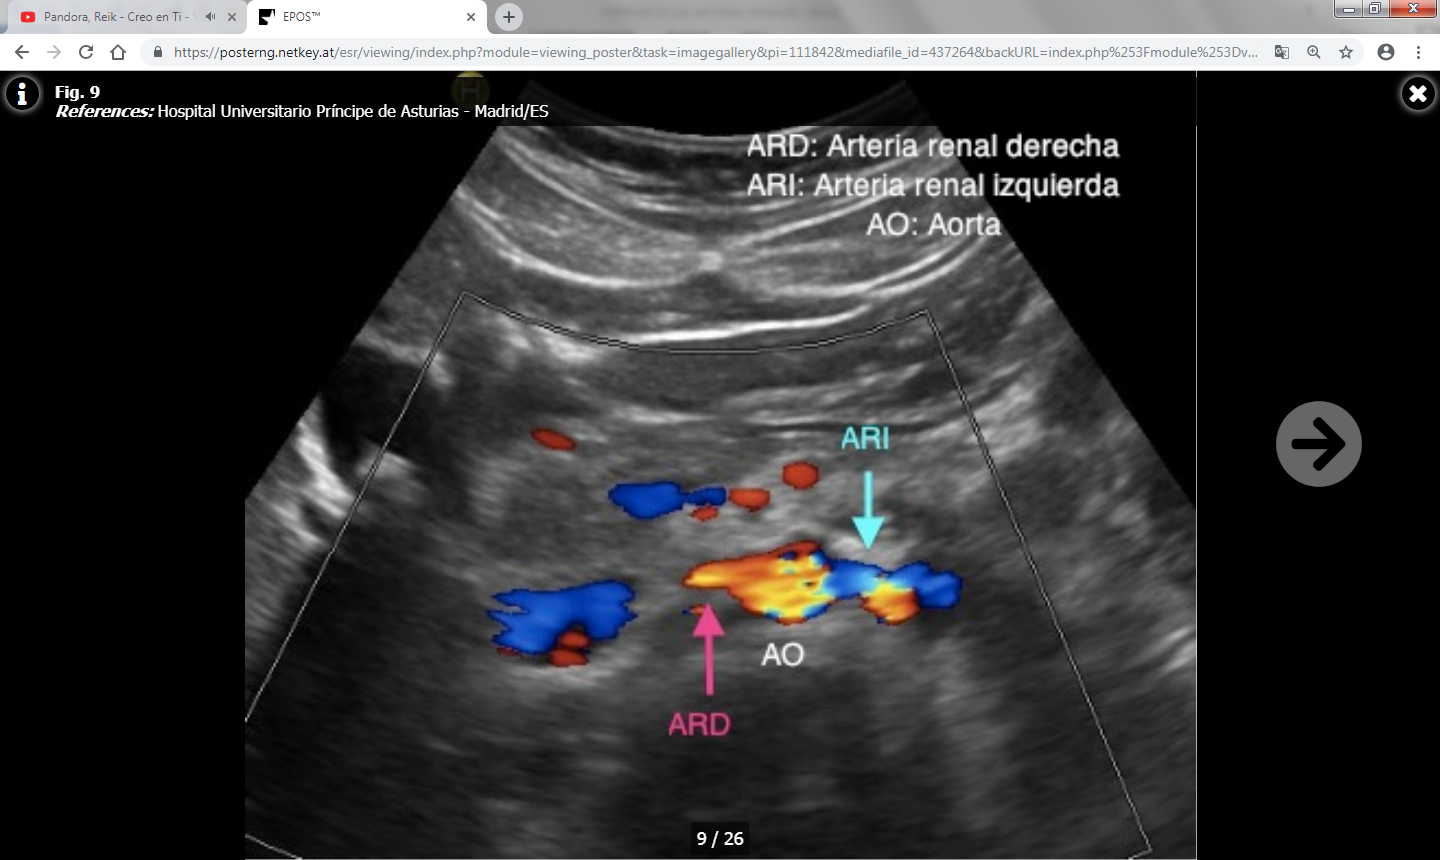

Hay dos grupos de parámetros: Directos o indirectos según se valoren en las arterias renales principales o ramas intrarrenales respectivamente.

Los parámetros directos son más fiables y reproducibles que los indirectos, y son los siguientes:

- Índice reno-aórtico (cociente entre la VPS de la arteria renal y la aorta): Normal por debajo de 3.5-3.6.